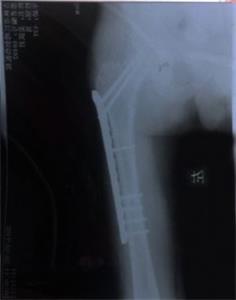

'姜跃军腿部术后照片'

姜跃军腿部术后照片